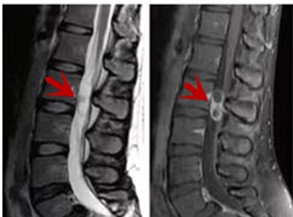

MRI利于磁場和射頻脈沖使體內(nèi)的氫原子核發(fā)生磁共振現(xiàn)象而產(chǎn)生的圖像,對軟組織的分辨率很高,對于脊髓、椎間盤、神經(jīng)、血管、韌帶、骨髓、腰部肌肉及周圍軟組織有很好的顯示效果,可以清晰的顯示腰椎間盤突出對硬膜囊、神經(jīng)根壓迫程度,以及骨折是陳舊還是新鮮,同時在脊髓病變(如脊髓損傷、髓內(nèi)出血或腫瘤)、椎管內(nèi)膿腫/血腫、椎旁肌肉軟組織病變等方面也具有優(yōu)勢,但是檢查時間較長,部分患者可能因體內(nèi)金屬植入物(如心臟起搏器、人工耳蝸等)而無法進(jìn)行檢查。

箭頭提示腰椎管內(nèi)腫瘤

紅色箭頭提示新鮮骨折,黃色箭頭提示陳舊性骨折